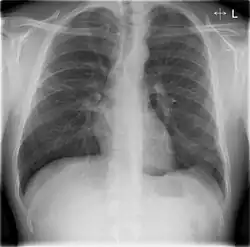

Chest X-rays and X-ray computed tomography (CT) can reveal areas of opacity (seen as white), indicating consolidation.[14] CAP does not always appear on x-rays, sometimes because the disease is in its initial stages or involves a part of the lung not clearly visible on x-ray. In some cases, chest CT can reveal pneumonia not seen on x-rays. However, congestive heart failure or other types of lung damage can mimic CAP on x-ray.[16]

When signs of pneumonia are discovered during evaluation, chest X-rays and examination of the blood and sputum for infectious microorganisms may be done to support a diagnosis of CAP. The diagnostic tools employed will depend on the severity of illness, local practices and concern about complications of the infection. All patients with CAP should have their blood oxygen monitored with pulse oximetry. In some cases, arterial blood gas analysis may be required to determine the amount of oxygen in the blood. A complete blood count (CBC) may reveal extra white blood cells, indicating infection.

X-ray findings indicating hospitalization include:

- Involvement of more than one lobe of the lung

- Presence of a cavity

- Pleural effusion